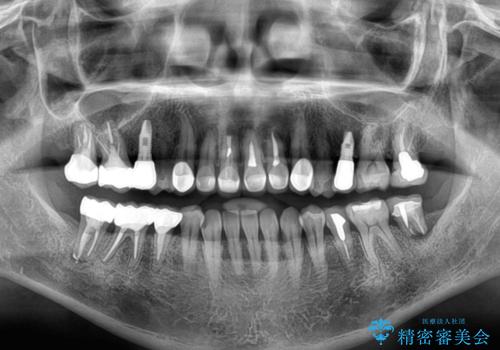

- 地元の歯科医院で治療を行っていたものの、難しいので都会に行くように指示をされたとのことで来院された患者様です。

右下のむし歯が歯肉縁下に及んでおり、歯周外科処置(歯冠長延長術)を行った上で、根管治療を行い、状態を整えて補綴治療を行うこととしました。

上顎前歯の根尖病変に痛みがありましたが、既に前歯が補綴治療済みであっため、外科的歯内療法(歯根端切除術)を行うことで解決することとしました。